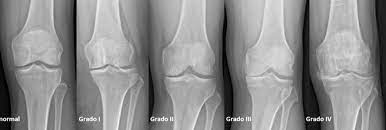

Artrosis de rodilla: eficacia y seguridad de la viscosuplementación

07 julio 2022

Existe evidencia concluyente de que la viscosuplementación conduce a una pequeña reducción en el dolor de la osteoartritis de rodilla en comparación con el placebo, que resulta menor a la diferencia mínima clínicamente importante. También hay evidencia concluyente de que la intervención se asocia con un riesgo aumentado de eventos adversos graves, por lo que se considera que estos hallazgos no respaldan su uso generalizado en el tratamiento de la artrosis de rodilla. British Medical Journal, 6 de julio de 2022.